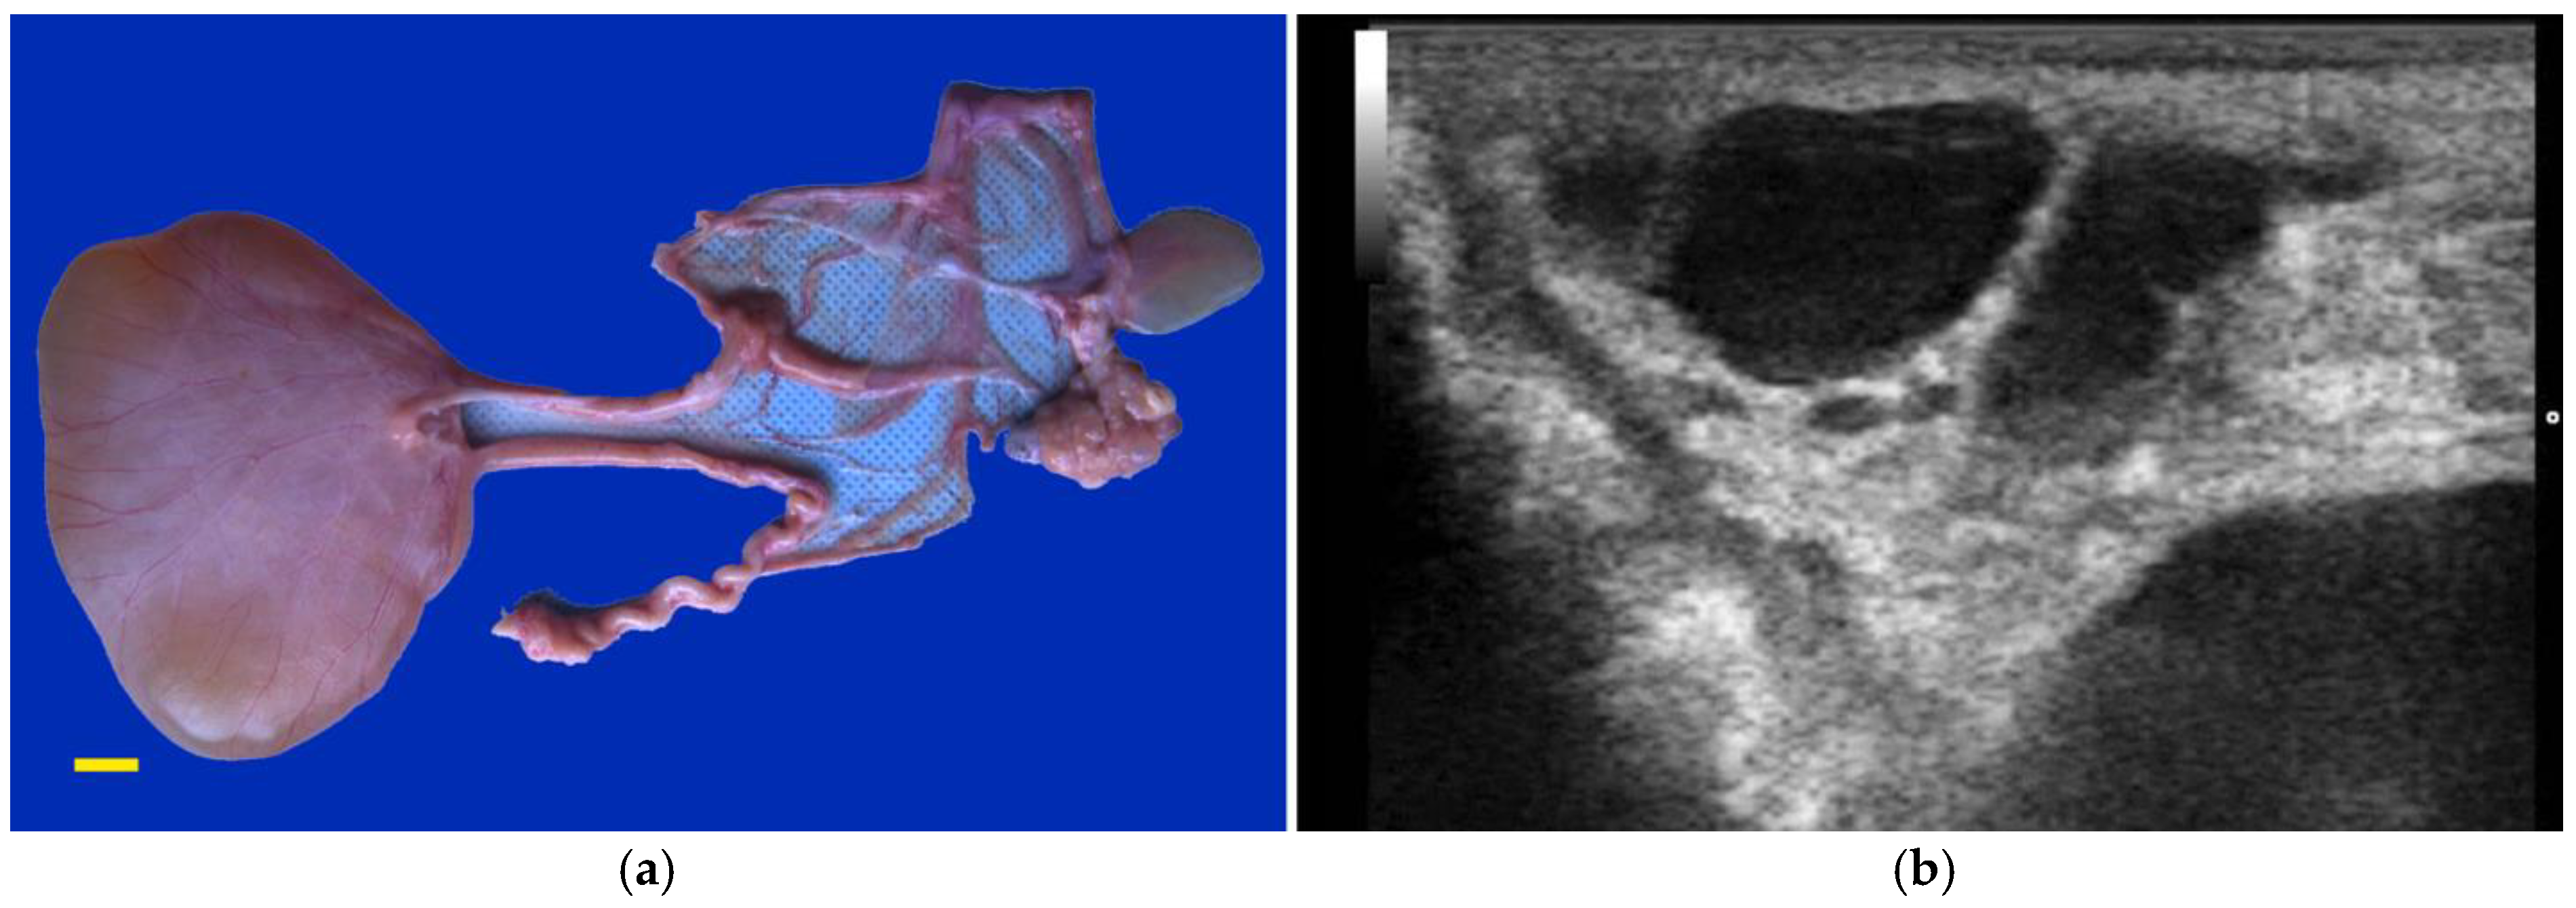

Segmental aplasia can affect any part of the tubular genitalia. An imperforate (persistent) hymen is the most common of these abnormalities. Affected females are presented with discomfort or tenesmus during mating. Transrectal ultrasonography reveals mucocolpos and mucometra (Figure 2). Other forms of segmental aplasia of the tubular genitalia include vaginal aplasia, uterus unicornis, and congenital hydrosalpinx due to segmental aplasia of the uterine tube (Figure 3) [6,7,14,28].

Figure 2. Ultrasonograms of mucometra due to an imperforate hymen in an alpaca. (a) cranial vagina (arrow); (b) cervical os (arrow) and uterine body.